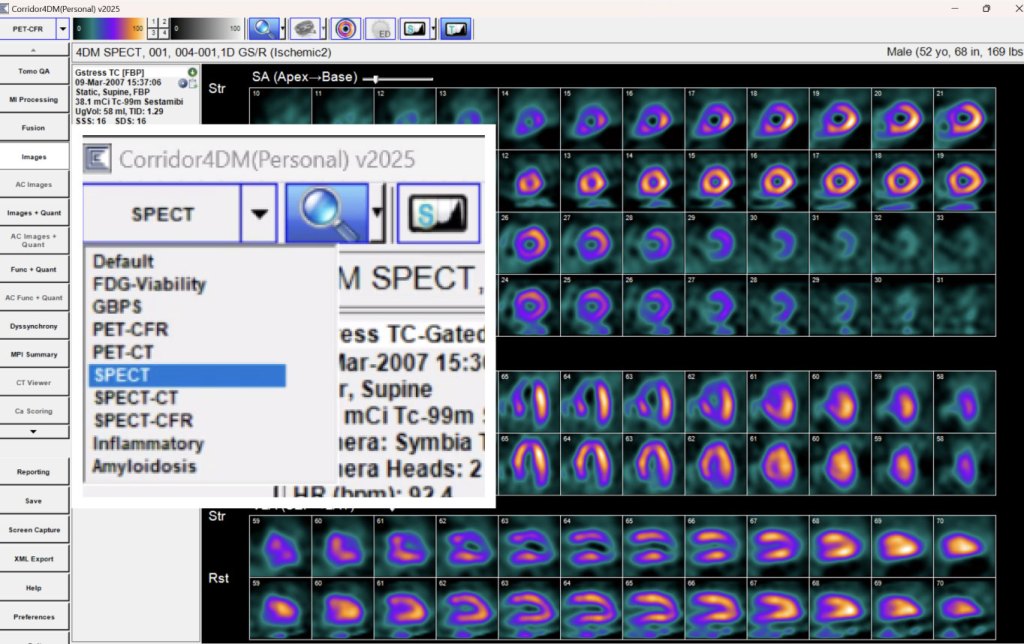

- SPECT MPI Workflow

- PET MPI Workflow

- Perfusion, Function, Viability in a Single Application

- Integrated Myocardial Perfusion with Function

- Segmental Scoring Overlays

Configurable screens and workflows

Quantification and reporting for all major workflows